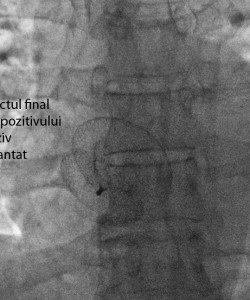

În data de 23 noiembrie 2015, în cadrul Cardiostructural Clinic din Spitalul Monza din Bucureşti au fost efectuate cu succes primele proceduri endovasculare ghidate prin ecocardiografie intracardiacă. Echipa medicală a Centrului de Intervenţii Structurale Cardiovasculare constituită din Dr Şerban Bălănescu, Dr Adrian Linte şi Dr Andrada Bogdan cu suportul tehnic al Dr Eustaquio Onorato de la Clinica Humanitas Gavazzeni, Bergamo, au realizat tratamentul endovascular cu închiderea unui defect septal atrial la o pacientă în vârstă de 49 ani şi a unui foramen ovale patent la o pacientă în vârstă de 17 ani, care a suferit un accident vascular cerebral ischemic recent.

Clasic pentru toate acestea se foloseşte ecocardiografia transesofagiană, care nu poate fi efectuată fără sedare profundă sau anestezie generală cu intubare orotraheală. Aceasta impune prezenţa în sala de cateterism a unui anestezist şi a unui ecocardiografist, medicaţie şi supraveghere complexă, precum şi îngrijirea pe termen scurt a pacientului intubat în terapia intensivă după ieşirea din sala de cateterism. Ecocardiografia intracardiacă se efectuează sub anestezie locală la pacient treaz, fără a necesita anestezist şi plasarea unei sonde de ecocardiografie în esofag. Aceste avantaje coroborate cu faptul că imaginile obţinute au o calitate superioară celor transesofagiene a făcut ca în multe săli moderne de cateterism ecocardiografia intracardiacă să înlocuiască ecocardiografia transesofagiană mai ales in cazul excluderii percutane a defectului septal atrial, a defectului septal ventricular, a foramenului ovale patent sau a puncţiei transseptale. Prin utilizarea unui sistem modern de ecocardiografie intracardiacă Cardiostructural Clinic din cadrul Spitalului Monza București, vine astfel în întâmpinarea nevoilor pacienţilor în ceea ce priveşte siguranţa şi confortul acestora precum şi îmbunătăţirea actului medical în sine. Ne propunem ca în viitor toate procedurile pe care le efectuăm pentru corecţia endovasculară a bolilor cardiace congenitale ale septului interatrial să fie realizate cu ajutorul acestei metode imagistice moderne, fiabile şi mai ales care conferă confort pacientului în timpul intervenţiilor endovasculare.

4_aspectul_final_proteza